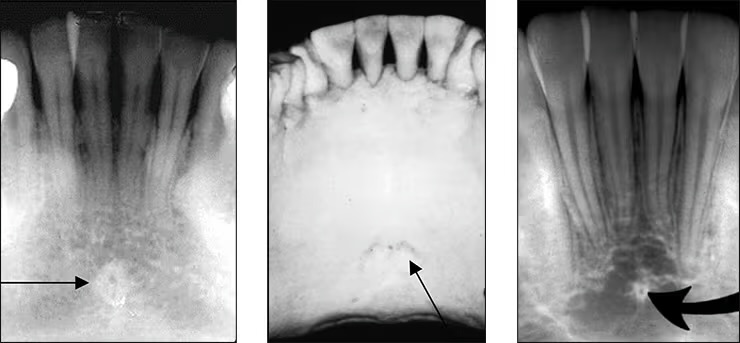

Lingual foramen

Small pinpoint opening in bone on the lingual aspect of anterior mandible.

Surrounded by genial tubercle.

(for lingual nerve and arteries)

Genial tubercles

aka mental spine

Spiny protuberance (sometimes 2) of bone located in the midline on the lingual aspect of mandible below roots of incisor teeth

Inverted Y

Depicts where the nasal fossa crosses the maxillary sinus (the boundary between them are shaped like a upside down Y)

Anterior Nasal Spine

Appears “V-shaped” or “triangular point”

Is a bony projection located at the base of the nasal septum in the maxillary midline